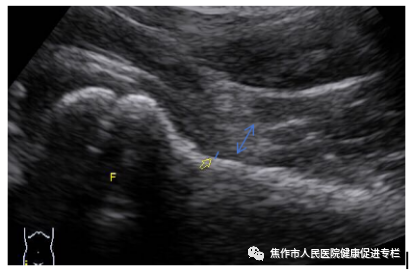

图1:右侧正常髋关节声像图,F:股骨头;蓝色箭头:关节囊厚度;蓝色短线:关节囊内积液深度,白色三角:关节囊外缘

图2:左侧髋关节关节囊形态外凸,厚度>6mm